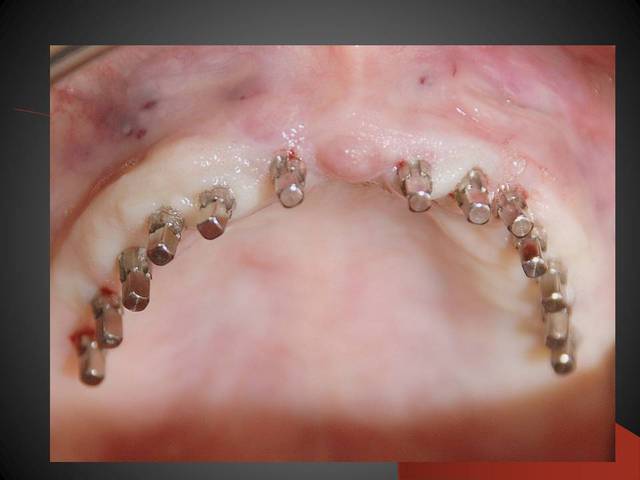

Les deux dernières photos montrent le même cas deux ans plus tard.

Tu as raison 8 auraient suffit normalement, mais l expérience nous a montré que les règles traditinelles ne sont pas valables pour les implants posés en minimal invasiv. En préservant le perioste on conserve une bonne nutrition peri implantaire et donc on peut faire des implants rapprochés sans danger ....

Il y a un livre d ailleurs très interessant et il existe en francais le titre doit être " implantologie flapless" , très documenté .Je l ai vu en vente à l ADF.